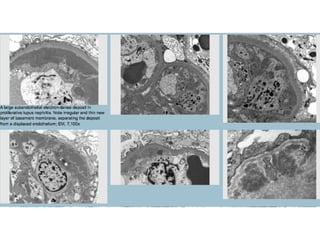

Electron microscopy:  Visceral epithelial cells: Different degrees of injury and degenerative changes; the effacement of foot processes is usually focal, but sometimes extensive Glomerular basement membranes: May show irregularities in thickness. Subepithelial “hump”-like deposits are characteristic of postinfectious GN; they may be sometimes large and confluent. “Spike” formation is not characteristic of this entity. Sometimes large subendothelial deposits and an intraluminal increase in inflammatory cells may be seen as well Glomerular endothelial cells: May show non-specific signs of injury and reactive changes; tubuloreticular structures are not seen Mesangium: Increase in cellularity and extracellular matrix, with sometimes large and confluent fine granular electron-dense deposits

Electron microscopy:  Visceral epithelial cells: Show different degrees of injury and degenerative changes, with focal, but sometimes extensive, effacement of foot processes. Subepithelial deposits can be seen in many cases Glomerular basement membranes: May be irregular in thickness, with the presence of intramembranous, subepithelial, and/or subendothelial deposits. Subendothelial deposits can be rather large and may demonstrate substructural organization ('fingerprint'-like pattern) Glomerular endothelial cells: May contain tubuloreticular structures Mesangium: Expanded by increase in cellular elements and extracellular matrix, with sometimes large and confluent fine granular, electron-dense deposits

Electron microscopy:  Visceral epithelial cells: Show different degrees of injury and degenerative changes; the effacement of foot processes is usually focal but sometimes extensive. Subepithelial and/or subendothelial deposits can also be present Glomerular basement membranes: May be thin; there is a higher incidence of thin glomerular basement membrane disease in IgA nephropathy than in any other glomerular disease {6} Glomerular endothelial cells: May show non-specific signs of injury; tubuloreticular structures are not seen Mesangium: Shows increase in cellularity and extracellular matrix, with fine granular electron-dense deposits that are sometimes large and confluent